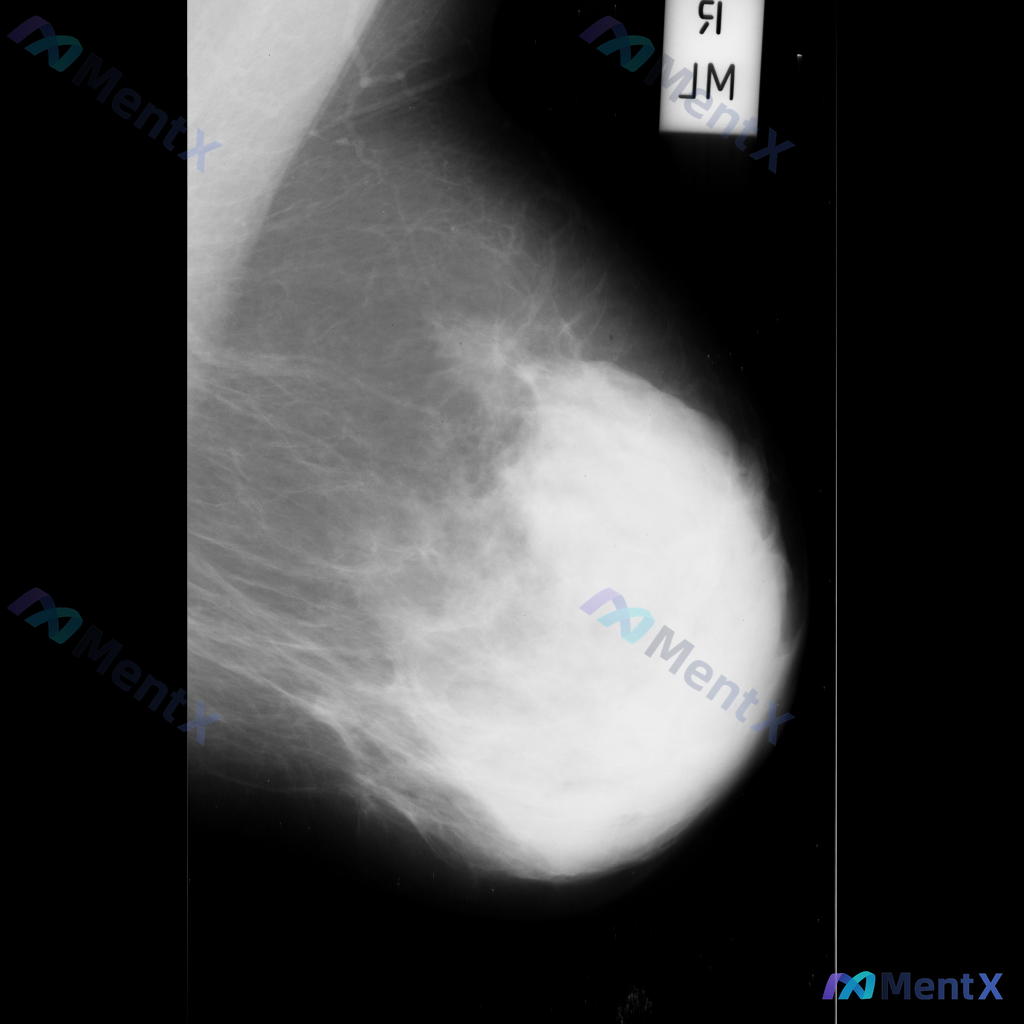

整理到一份乳腺钼靶影像资料,主要表现如下: - 乳腺中后部可见局灶性结构扭曲 - 无明确的肿块核心 - 周围腺体和脂肪界面被不规则牵拉 目前暂不提供既往影像对比和详细病史(手术史、外伤史、炎症史等)。 这种表现大家会先怎么判断?更倾向于往哪种方向考虑?

整理到一张乳腺钼靶影像的分析资料,大家可以先基于现有信息讨论一下。 基本影像学表现 - 可见形态不规则的致密区域,伴有结构扭曲和模糊边缘 - 背景乳腺腺体呈 BI-RADS B/C 型(致密性增加) 目前从影像上看,存在几种可能的方向,想听听大家的第一判断:单看这组影像学表现,你会先考虑哪一种异常方...